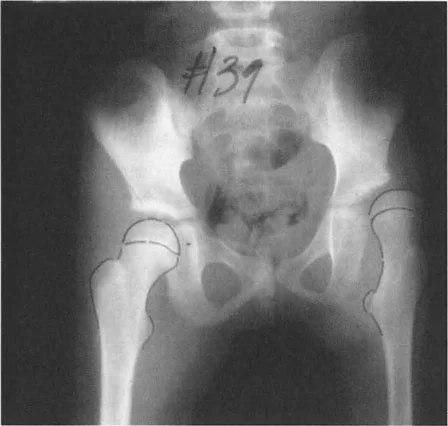

إذا كان المريض يعاني من تشوه تقوس (Varus) في عظم الساق أو الفخذ، فإن متجه رد فعل الأرض يتحرك نحو الداخل (إنسيًا). كلما مر متجه رد فعل الأرض أكثر إنسيًا بالنسبة لمركز الركبة، زاد عزم دوران التقريب. وهذا يزيد بشكل كبير من قوى الضغط على الجزء الإنسي من سطح عظم الساق القريب (medial tibial plateau).

بينما يحمل الوقوف على ساق واحدة طبيعيًا الجزء الإنسي بحوالي 75%، فإن تشوه التقوس الشديد (الذي يسبب انحرافًا كبيرًا في المحور الميكانيكي، أو MAD) يمكن أن ينقل 100% من الحمل إلى الجزء الإنسي. على مدى فترات طويلة، يؤدي هذا التحميل الميكانيكي الموضعي المفرط إلى تدهور سريع وتدريجي للغضروف المفصلي، وتصلب تحت الغضروف، وتكون نتوءات عظمية، وفي النهاية إلى التهاب مفصل الركبة في مراحله المتأخرة.